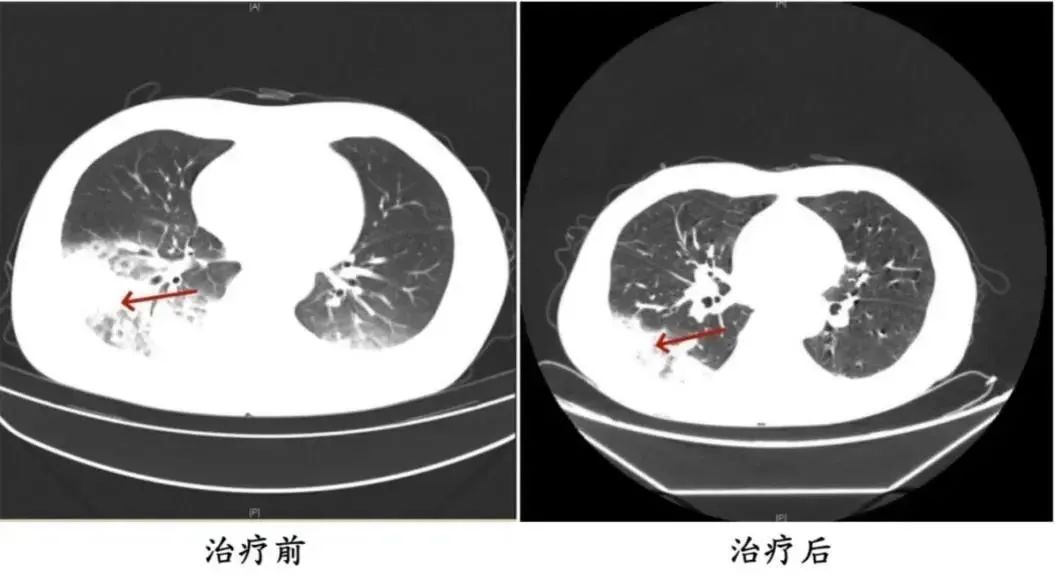

李先生的经历并不少见。2024年,湖南省长沙市55岁的市民陈先生有许多既往历史,如2型糖尿病、2型糖尿病性肾病、慢性肾功能不全等。他去医院看病,因为他继续发烧、发抖、干咳,发现肺部感染严重。

医生询问后发现,陈先生之前开车出差。由于天气炎热,他开始了一台很久没有清洗的汽车空调。他每天在车里呆十几个小时,回来后就出现了上述症状。经检查,最终确诊为军团菌肺炎。

治疗前后陈先生肺部CT影像